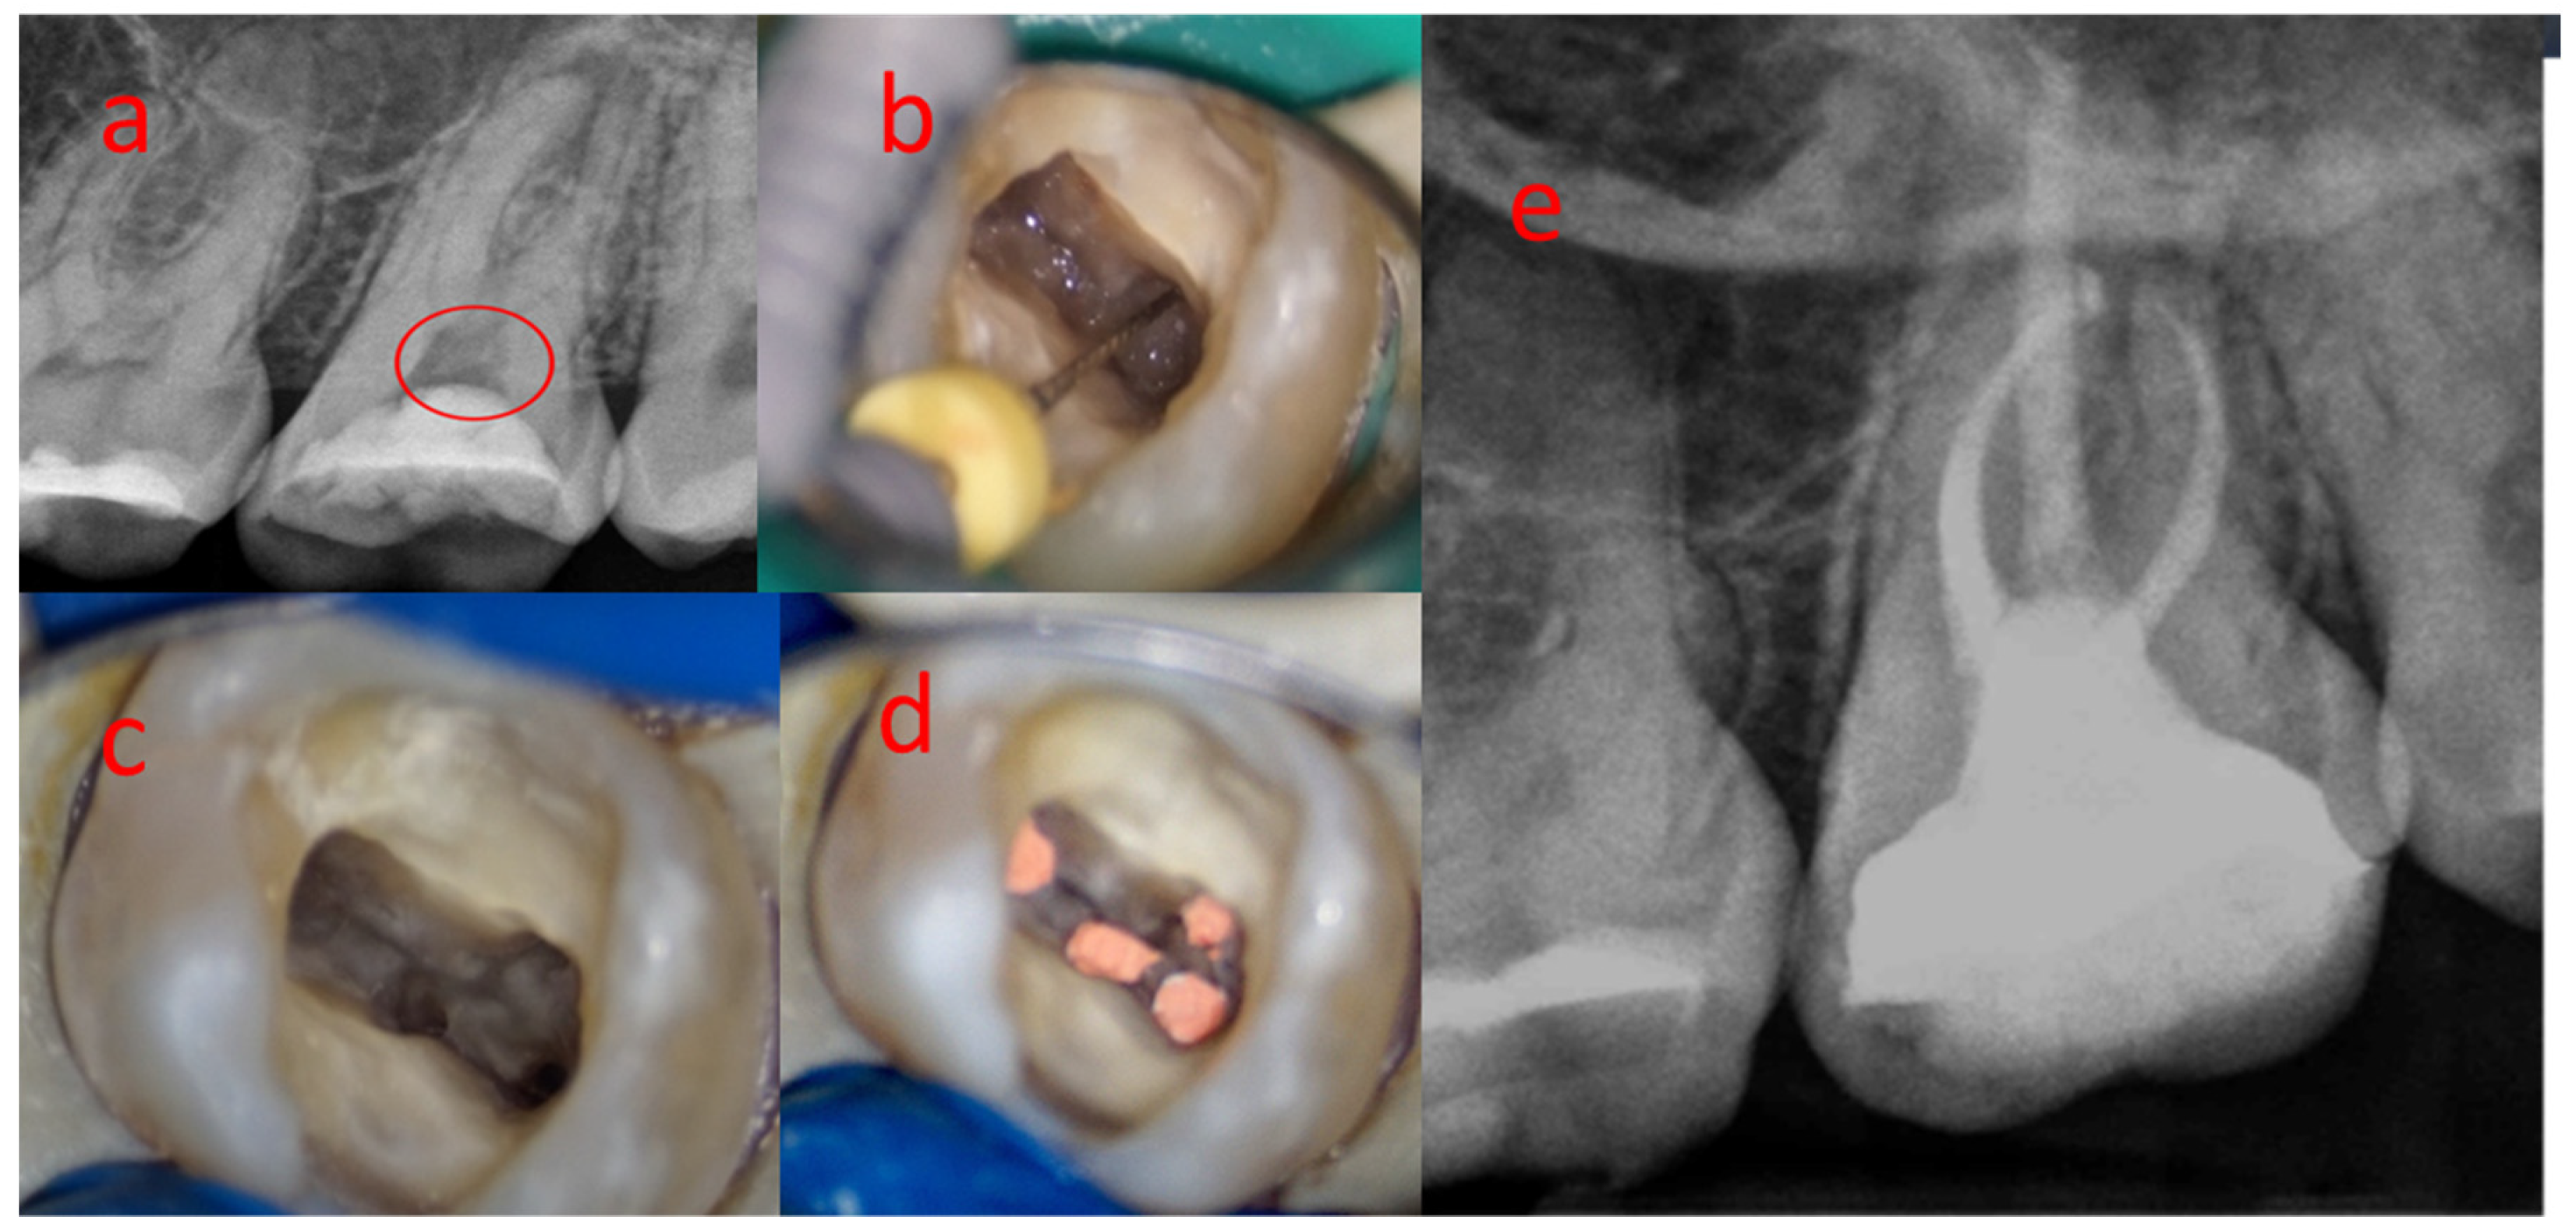

3.1. Sample 01

3.4. Sample 04